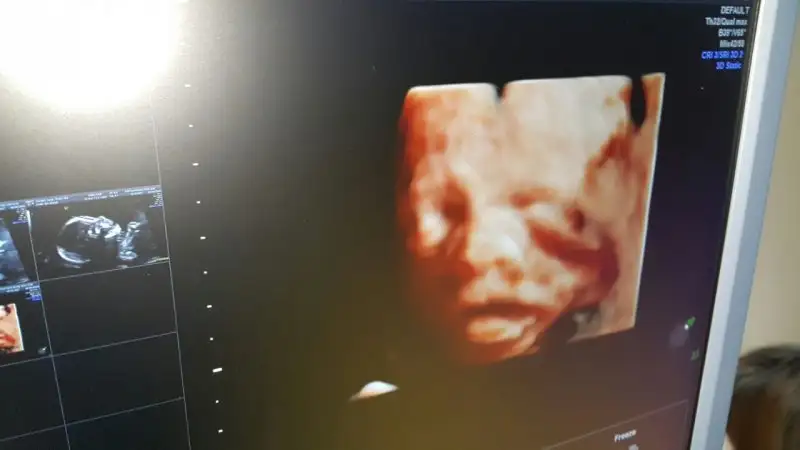

Cok güzel bir bebek masallah ne kadar belirgin benim ultrasonumdada ınsallah böyle güzel net pozlar verir bebisimKızlar dün detaylı ultrasonum vardı babası da bende kızımızı gördük. sağlık ile alakalı hiçbir sorunu yok herşey çok iyi dedi doktor

Cok güzel bir bebek masallah ne kadar belirgin benim ultrasonumdada ınsallah böyle güzel net pozlar verir bebisim

Maşallah canım yine de baya net..Bizimki elini yüzüne kapatıyor genelde.rahatsiz oluyorlar heralde.Eki Görüntüle 1968282 Eki Görüntüle 1968283 Bende bu saatte uyuyamayınca yazılanları okudum. Bizim ultrason fotomuzda çok net olacaktı ama inatla ellerini çekmedi yüzünden arasından çekiverdi doktorumuz. Bu da bizim Duru bebeğimiz. İsmini çok önceden koymuştuk ama maşallah çok varmış bu ismi koyacak :)